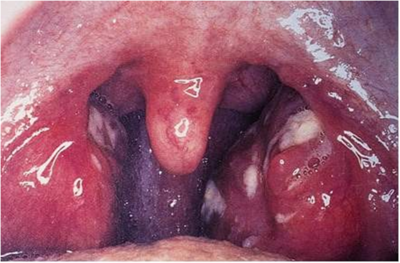

Consulta paciente de 15 años por cuadro de 3 días de evolución caracterizado por odinofagia brusca, tos seca, CEG, mialgias y sensación febril no objetivada. Al examen físico se palpan adenopatías cervicales anteriores dolorosas y blandas y en la faringe se evidencia la imagen adjunta. ¿Cuál es el diagnóstico más probable?

Answer

• Faringitis Aguda

• Mononucleosis Infecciosa

• Sinusitis Aguda

• Amigdalitis Pultácea